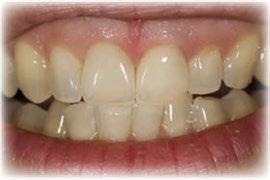

Acude a la consulta un paciente masculino de 35 años exigiendo cambios en la estética de sus dientes. El examen intraoral clínico y fotográfico reveló pérdida de estructura dentaria con facetas de desgaste en dientes anterosuperiores e inferiores, acentuándose hacia zonas oclusales de dientes posteriores.

El diagnóstico evidenció que el paciente presentaba alteración en la dinámica de la guía anterior por el desgaste de los bordes incisales, con pérdida de dimensión vertical oclusal (VDO), alteración del plano de oclusión y relaciones interoclusales inestables (Figuras 1 y 2)

Figura 1. Caso inicial. Figura 2. Vista oclusal superior.